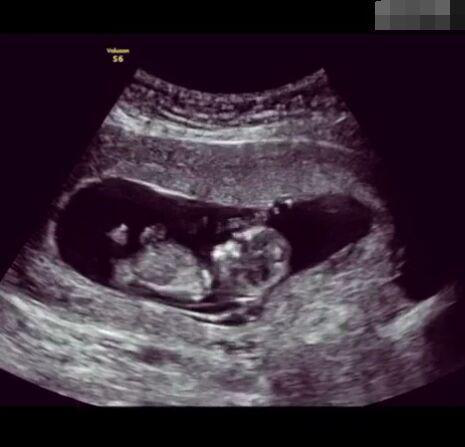

那些做了B超檢查確定胎兒男女,生下來后發(fā)現(xiàn)不對的,多半是因為在B超檢查時寶寶太調皮,以致影響了檢查準確性。就比如說,有的女寶寶在媽媽肚子里玩自己的臍帶,把臍帶夾到了兩腿中間,B超就有一定幾率拍出來好像是男寶寶的特征,導致被誤認為是男孩子。還有些男寶寶過分害羞,在做B超時雙腿緊緊并攏,醫(yī)生也很難判斷男女,只好大致猜測是女孩,就又造成了誤會。因此,B超亦不是萬能的。